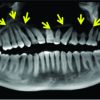

Clavicles were non-tender on palpation and there was no local rise of temperature. There was no tenderness in both sternoclavicular joints and acromioclavicular joints. The swellings were hard in consistency with smooth surface and ill-defined margins. On examination, both shoulders range of motion (ROM) were normal. There was no distal neurovascular deficits. Systemic examination was unremarkable. X-ray showed expansile sclerotic lesion on the medial half of clavicles bilaterally. Blood investigations were done which showed raised erythrocyte sedimentation rate (ESR-90), C-reactive protein – 0.6, total count – 8000. Antistreptolysin O titer (ASO) was negative. Peripheral smear was normal. Hemoglobin electrophoresis was normal. Sickling test was negative. Rheumatoid arthritis (RA) factor and anti-cyclic citrullinated peptide were negative. Mantoux test and sputum acid-fast bacillus (AFB) were also negative. Liver function test and renal parameters were within normal limits. Chest X-ray was otherwise within normal limits (Fig. 2). No abnormalities were noted in ultrasonography (USG) abdomen. Magnetic resonance imaging (MRI) showed expansile lesions in bilateral (medial aspect) clavicles – possibility of CRMO (Fig. 3). We proceeded with biopsy. Specimen was sent for histopathologic examination and culture. Culture showed no growth. Histopathological examination showed mainly ossifying bone with foci of hemorrhage.